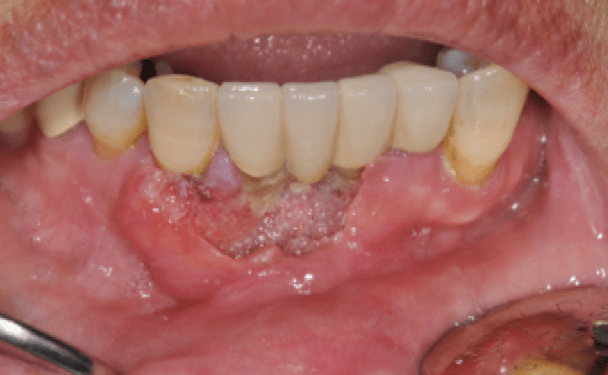

- 입안에 하얀 또는 붉은 병변이 있다.

구강내 점막에 지워지지 않는 백색 병소가 있는 것을 백반증이라고 하는데, 이러한 백반증이나 붉은 홍반증 등은 구강암으로 진행될 수 있는 병소로 필요한 경우 조직검사를 시행하여 정확한 감별을 시행하여야 합니다.

치은암![]() |